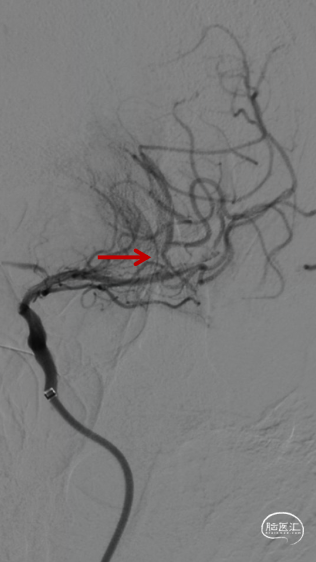

微导管微导丝携SKATHI远端通路导管负压状态下再次进入颈内动脉,造影确认颈内动脉通畅,大脑中动脉中远段可见栓塞。

微导管越过大脑中动脉血栓后,以4-20mm Solitaire AB支架,配合6F 115cm SKATHI远端通路导管取栓一次,复查造影大脑中动脉血栓通畅,远端仍有少许血栓,观察后血流能够维持。